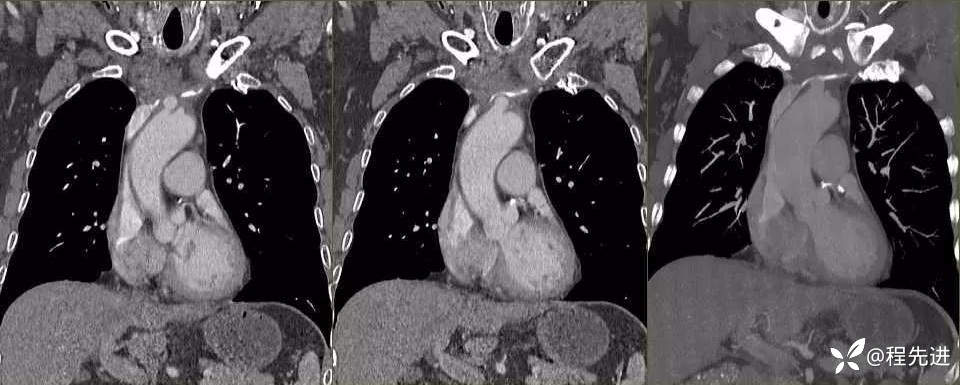

平扫纵隔窗

增强

动脉期

冠状位MPR+MIP